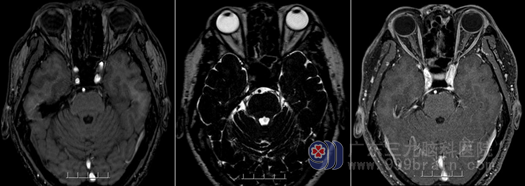

神经外十科主任欧阳辉欧阳辉教授在查看了其病情后,认为李先生的疼痛虽然不是三叉神经痛的常见部位:第二、三支分布区,李先生的疼痛位于右颞部,但疼痛的性质确实属于三叉神经痛,为了解除李先生的痛苦,欧阳教授决定对其进行根治性的手术治疗。李先生在入院完善了相关检查,欧阳辉主任带领的医疗团队为其进行了微创的“右侧三叉神经根显微血管减压术”,术中医生在显微镜放大下,找到了李先生三叉神经痛的原因:有责任血管压迫三叉神经出入脑干区(REZ区),精准地分开责任血管后,用特氟龙(teflon)棉丝将血管与神经分隔开。手术后李先生的右颞、面部疼痛感觉完全消失了,目前有轻微的麻木感(很快可以恢复),无任何其他术后并发症发生。